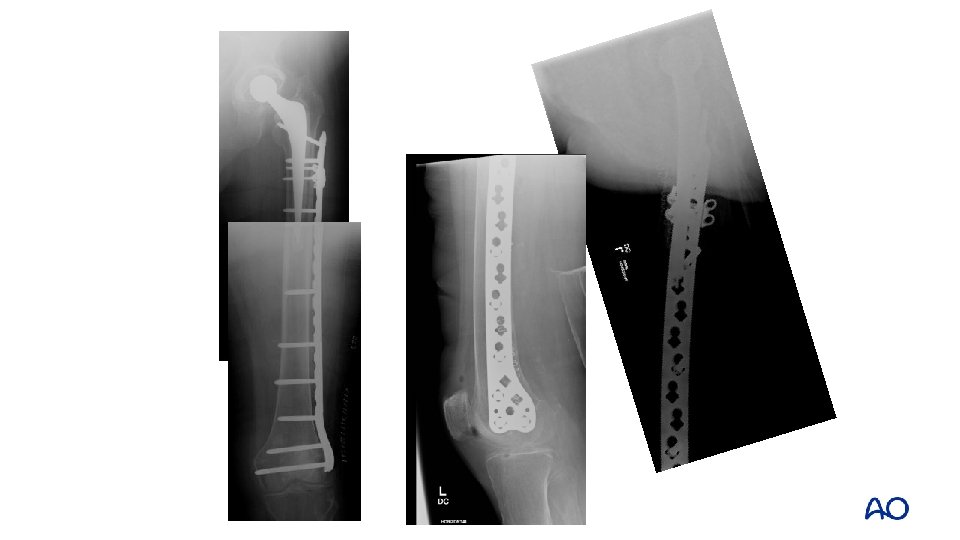

• 91 -year-old patient • Type B 2 fracture • Lives with retired daughter • Wheelchair bound • ASA IV

• Preoperative plan? • Keep patient alive, maintain ability to transfer, minimize surgery, and keep implant • Relative stability • Lateral plate (lateral) + strut (medial or anterior) • Immediate mobility

Type B 2—preoperative plan • Relative stability • Intramedullary fixation (new stem) • Supplemental extramedullary fixation • Lateral plate • Medial/anterior strut

Technique Option 1: Reconstruct tube around new implant Option 2: Place new implant into reconstructed tube Option 2 shown

Option 2: fixing the tube first

Reconstituting the tube first: intracortical screws • Not reported • Avoid excessive stripping • • AO reduction “towel clips” only—no lobster claws, etc 2 mm screws • Drill through with 1. 1 mm first, then over drill

Reconstituting the tube Lateral plate (or strut) • Proximal cerclage wires • Distal screws if possible Cortical strut • (Medial or anterior) • Shaped with burr to fit • Bone graft around edges